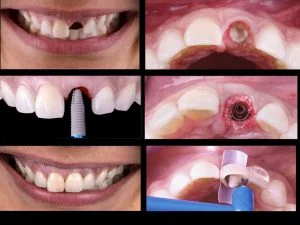

When you lose a tooth, you lose both the root and the crown. To replace the tooth, the surgeon first replaces the root with a  dental implant. Time is allowed for bone to heal and grow around the dental implant. The bone bonds with the titanium, creating a strong foundation for artificial teeth.  A support post (abutment) is then placed on the implant and a new replacement tooth (crown) is placed on top of the abutment. In many cases, a temporary replacement tooth can be attached to the implant immediately after it is placed. If all of your teeth are missing, a variety of treatment options are available to support the replacement teeth.

Before & Afters of Dental Implant Patients

Complete Dental Implant Cases Gallery

General Disclaimer: The results in the photographs are examples only and do not imply any certainty of the result of a procedure, and all outcomes are subject to the circumstances of the individual patient.